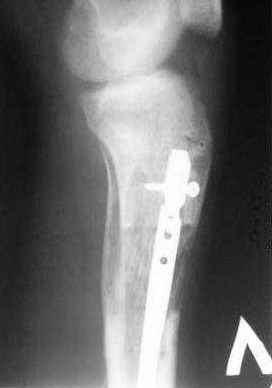

5. Ну и чтобы не быть голословным. Молодой человек подорвался на фугасе (Чечня, 2005 год). Свежие рентгенограммы:

Соответственно ожоги и дефект мягких тканей, переломы костей стопы и пр. Наложили аппарат

Илизарова (как придется), хирургически обработали и героически заживляли мягкие ткани с многочисленными кожными пластиками. В итоге через полгода я принял его вот таким:

Реализовал описанную выше методику, и в итоге вот что получилось. Высылаю лишь прямые проекции,

в боковых тоже всё в тему.

Очень пригодились карбоновые кольца (Джолдас -огромное спасибо, я твой должник!!!), поскольку остеопороз дистального отломка был просто невероятный. На цифровом рентгене с трудом угадывались контуры.

Рентген в процессе перемещения - внизу карбоновые кольца, тракция фрагмента спицами с упором.

внешний вид в аппарате - не завершающем этапе, сначала стопа тоже была фиксирована в аппарате.

Сейчас аппарат сняли, но случай ещё не завершенный.

Признаюсь честно, не совсем уверен в прочности консолидации на стыке косточек. Кроме того, укорочение в районе 6 см. Сейчас реабилитация - ходит опираясь на ногу с одним костылем.

Продолжение, видимо, будет... Возможно, будем удлинять.